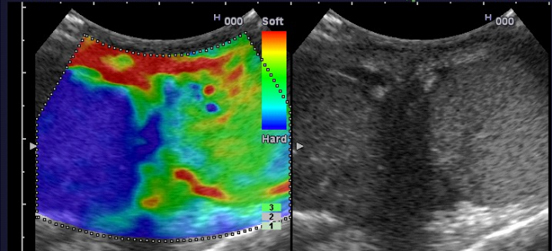

Вне зависимости от локализации новообразования злокачественный процесс характеризовался высокой степенью жесткости ткани и находит свое отражение на цветовой шкале прибора в виде участка интенсивного синего цвета, тогда как, обычные или доброкачественные новообразования представлены в виде участков зеленого или красного цвета. Данные эластографии служат важным дополнительным критерием оценки характера изменений в тканях различных органов и помогают в дифференциальной диагностике новообразований различных локализаций.

Качественные и количественные изменения нормальной или обычной структуры ткани органа под влиянием ультразвукового сигнала при эластографии отражаются в виде цветовой шкалы и могут быть подсчитаны при помощи количественных показателей. При выполнении стандартного ультразвукового исследования на второй части монитора в режиме «реального времени» получают эластограммы, которые оцениваются по компьютеризованной цветовой шкале, где степень жесткости соответствовует определенному цвету (мягкие ткани - красный и зеленый цвета, твердые - синий), а также по стандартной бальной шкале жесткости, которые разработаны применительно к исследуемому органу.

Со времен Гиппократа известно, что высокая плотность или жесткость новообразования рассматривается как показатель его злокачественности. Именно этот принцип положен в основу нового ультразвукового метода эластографии, когда с помощью ультразвуковой волны и небольшой механической компрессии можно определять степень деформации ткани органа. При этом мягкие части ткани будут деформироваться в большей степени, а твердые в меньшей.